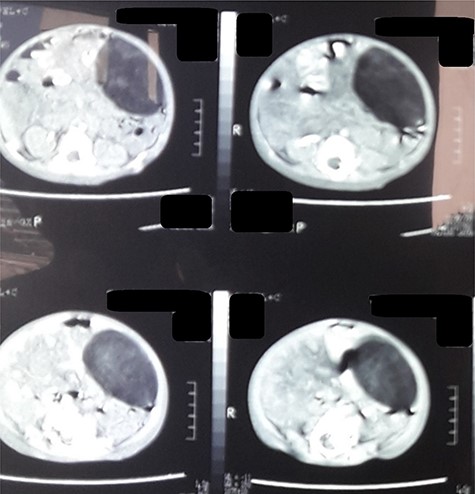

Computed tomography (CT) of the abdomen revealed a homogeneous, well vascularized mass measuring 9.4 × 10.6 cm and encapsulated with thin septation in its medial part. The mass was located in the upper left quadrant and extended to the pelvis with an oval appearance (Fig. 1). Other abdominal findings were normal. Under general anesthesia, an incision was made in the midline above the umbilical region. The findings were a soft, yellow mass with defined margins, originating from the small intestine’s mesentery, 30 cm from Treitz ligament (Figs 2 and 3). Complete excision of the mass was performed without intestinal resection (Figs 4 and 5). Histopathology showed a normal adipose tissue composed of mature adipocytes with no evidence of mitosis or nuclear atypia, which confirmed the presence of the mesenteric lipoma (Fig. 6). Oral feeding was started 2 days after the operation, and the patient stayed in hospital for 5 days. He was discharged in a good condition with normal bowel movement. The child was evaluated 4 months after the procedure. He had no complains, and abdominal ultrasound revealed normal findings.

CT scan of the abdomen revealed a fat density mass with defined margins filling the left abdomen and shifting the small bowel to the right.